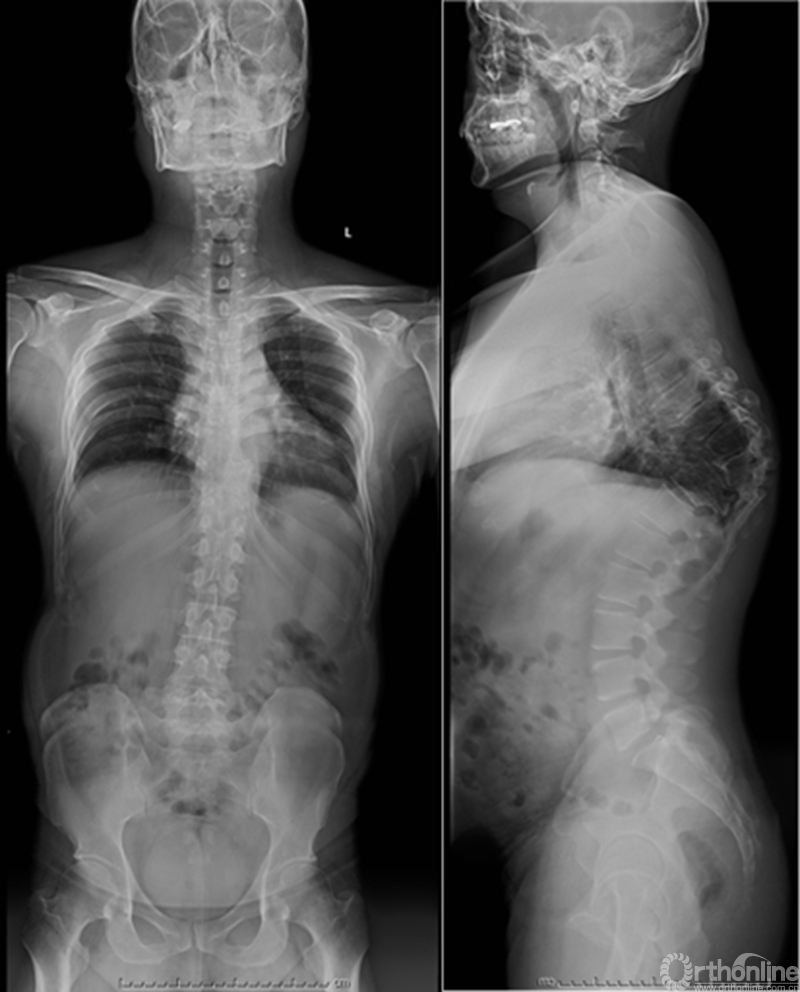

众所周知,脊椎结核后突畸形是结核病严重的后遗症之一。不仅影响患者外表仪容和心理,还可能出现晚发病灶造成截瘫。30多岁的小李就是一位脊柱结核后造成后凸畸形伴截瘫的患者,其畸形角度高达90度。针对此类患者的治疗大多就是截骨矫形,手术创伤大不说,椎体切除后造成的脊柱失稳等一系列后遗症也是令医生和患者担忧的。为解决临床上的这类问题,丁文元教授对传统的PVCR截骨技术进行了简化和改良,即后路单侧截骨部分椎体切除固定矫形术(UPVCR)入路,该技术采用后方单侧截骨,切除部分椎体、相邻椎间盘大部,保留对侧椎弓根及部分椎体,重建置入钛网支撑。随后,丁文元教授通过UPVCR技术对小李实施了手术,经过家人悉心地照顾,小李术后肌力恢复的良好,很快就出院了。三个月复查时竟是自己走路来的,临床疗效让患者及家人很是满意。

患者术前资料

患者术后资料

丁文元教授介绍说,UPVCR技术的优势在于手术操作简单,易于掌握,学习曲线短,手术时间短,出血少,神经并发症少;临床应用时极少发生断钉、断棒、不融合的现象,术中保留了良好的血运、植骨床,提供骨生长环境,保证部分骨支撑,术后极少发生矫正丢失,临床效果肯定。